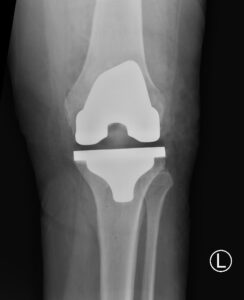

Knee Procedures Total Knee Replacement A knee replacement is a surgical procedure in which damaged or worn-out parts of the knee joint are removed and replaced with artificial components. It is typically done to reduce pain and improve function in people with severe knee joint damage, often caused by arthritis or injury. Partial Knee Replacement A knee replacement is a surgical procedure in which damaged or worn-out parts of the knee joint are removed and replaced with artificial components. It is typically done to reduce pain and improve function in people with severe knee joint damage, often caused by arthritis or injury. Revision Knee Replacement Revision knee replacement is a surgical procedure to replace or repair a previous knee prosthesis that has become loose, worn out, or infected. It involves removing the old implant and installing a new one to restore knee function and relieve pain. High Tibial Osteotomy High tibial osteotomy is a surgery that involves cutting and reshaping the upper part of the shinbone (tibia) to realign the knee joint. It is often performed to relieve arthritis pain in young, active patients by shifting weight away from damaged cartilage. ACL Reconstruction ACL reconstruction is a surgical procedure to replace a torn anterior cruciate ligament (ACL) in the knee with a graft, usually taken from the patient's own tissue or a donor. It aims to restore stability and allow return to normal activity levels following ligament injury. Meniscal Surgery Meniscal surgery involves repairing or removing damaged meniscal cartilage in the knee, which cushions and stabilizes the joint. The procedure can help relieve pain, restore knee function, and prevent further joint degeneration. Patellofemoral Stabilisation Patellofemoral stabilisation is a procedure to realign or secure the kneecap (patella) when it tends to dislocate or drift out of place. It aims to improve knee stability and prevent recurrent dislocations or pain.